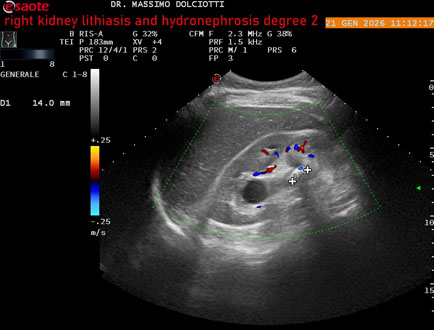

Data inserimento: 22/01/2026

Ecografia del: 21/01/2025

Strumento: Esaote MyLab Eight

Sonda: Convex Multifrequenza 1-8 MHz

Età Paziente: M 27 anni

Motivazione dell'esame: dolore al fianco destro da 3 mesi.

Commento all'esame: le immagini ed il video documentano il rene destro in sede, con ecostruttura disomogenea per evidenza, alla pelvi renale, di immagine iperecogena delle dimensioni di 16,2 mm, con cono d'ombra posteriore, da ricondurre a litiasi ed una formazione simile, di minore entità, al polo inferiore, delle dimensioni di 6,8 mm. Rene dx con diametro longitudinale di 122 mm (v.n. 90-120 mm) x 63 mm e parenchima renale dello spessore di 15 mm (v.n. > 13 mm). Rene dx con idronefrosi di 2° grado.

Conclusioni: litiasi e idronefrosi di 2° grado al rene destro (lithiasis and second-degree hydronephrosis of the right kidney).

In collaborazione: Dr.ssa Marica Manfredi - Ancona, Dr. Ilir Qose - Ancona

Presentazione: Dr. Massimo Dolciotti - Ancona

Elaborazione digitale: Andrea Dini - Ancona